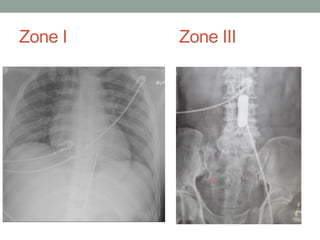

Zone I Zone III

• X-ray – confirmation balloon position: 2 radiopaque bands

• Zone I – T4 to L1

• Zone III – L2 to L4

Procedure Steps • AccessCommon Femoral Artery (CFA) using ultrasound (or cutdown) • Zone I – Xiphoid (approx 50cm) • Zone III – Umbilicus (approx 40cm) • Inflate balloon until moderate resistance (document time) • Zone I – 15 to 20 mL • Zone III – 10 to 15 mL • X-ray – confirmation balloon position: 2 radiopaque bands • Zone I – T4 to L1 • Zone III – L2 to L4 • Secure catheter • Expedite departure to OR/IR (no CT post-REBOA)